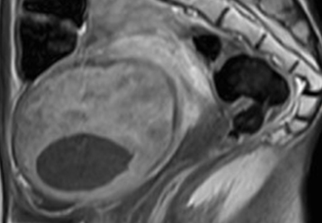

자궁근종 비수술 하이푸 치료 후 분만사례입니다. 자궁근종 하이푸 치료는 자궁근종 부위만 선택적으로 치료하는 시술로 자궁근종 전체적으로 시술하였습니다. 8cm 액화변성 자궁근종 하이푸 치료 시간은 57분이...